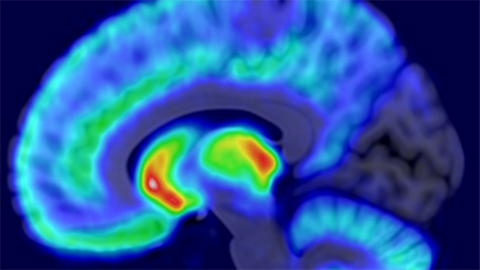

The study was conducted by using positron emission tomography (PET) and functional magnetic resonance imaging (fMRI). The participants were injected with radioactive compounds that bind to their brain’s opioid and dopamine receptors. Radioactivity in the brain was measured twice with the PET camera to map the distribution of opioid and dopamine receptors. Subsequently, the participants’ brain activity was measured with fMRI while they viewed videos depicting humans in various painful and painless situations.